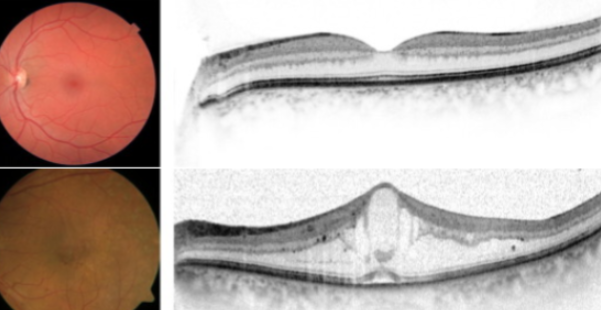

O que é o edema macular diabético:

O edema de mácula diabético, ou seja, o inchaço da parte central da retina, É A PRINCIPAL CAUSA DE BAIXA DE VISÃO NOS DIABÉTICOS!

Se lembrarmos que a visão é composta pela parte central, ou foco da visão, e parte periférica, ou campo de visão, o edema macular acomete o foco da visão, enquanto a retinopatia diabética acomete o campo de visão.

Por este motivo, quem tem edema de mácula diabético percebe facilmente a piora da visão, principalmente na leitura. Já quem tem uma retinopatia diabética, que pode ser inclusive avançada, pode muitas vezes não ter queixas visuais. Um indivíduo pode ter somente retinopatia diabética sem edema, somente edema macular sem retinopatia ou ainda ter a doença mista (edema + retinopatia).

A mácula é a parte importante, portanto também a mais vascularizada da retina. Logo, tende a sofrer mais com doenças vasculares. A parede dos vasos danificada junto com a formação de microaneurismas permitem o extravasamento de líquido dos capilares sanguíneos para dentro da retina.

Este líquido se acumula nesta região, causando o edema da mácula (Figura 10). Em 20 anos de doença, em torno de 30% dos pacientes diabéticos terão edema macular.

É um exame super disponível, barato, e que envolve pouca tecnologia. Quando há edema macular diabético, normalmente usamos a tomografia óptica da mácula e retina (OCT) para diagnosticar, quantificar (analisar se o edema é leve, moderado ou grave), avaliar o prognóstico através de marcadores tomográficos de boa ou má recuperação da visão, bem como acompanhar a efetividade do tratamento.